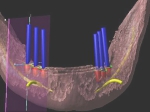

術前術前骨の高さが不足している場合、通常のインプラントでは処置が不可能なものが多い。特殊なショートインプラントを用いて可能になる例。 術前 術前CT像術前CT像術前CT像、下歯槽神経が下あごの中央部を走行しているため利用できる骨の高さが少ない。 埋入予定計画埋入予定計画埋入予定計画 術後レントゲン術後レントゲン、ひだりは少し神経をおそれすぎてやや埋入深度が不足、しかしこれでもしっかりと骨と固着した。